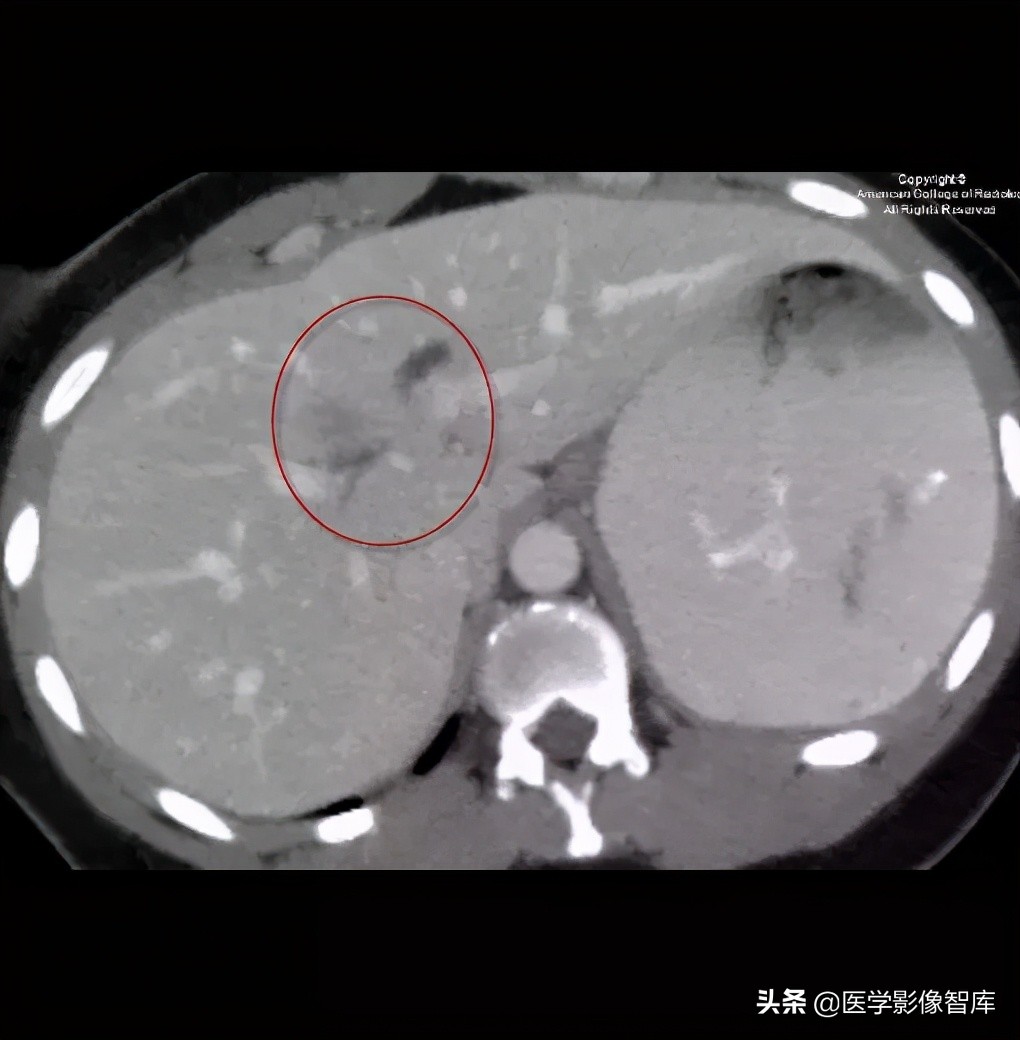

图 4. 轴位 CT 显示肝内胆管轻度扩张,相关的症状及实验室检查未发现异常